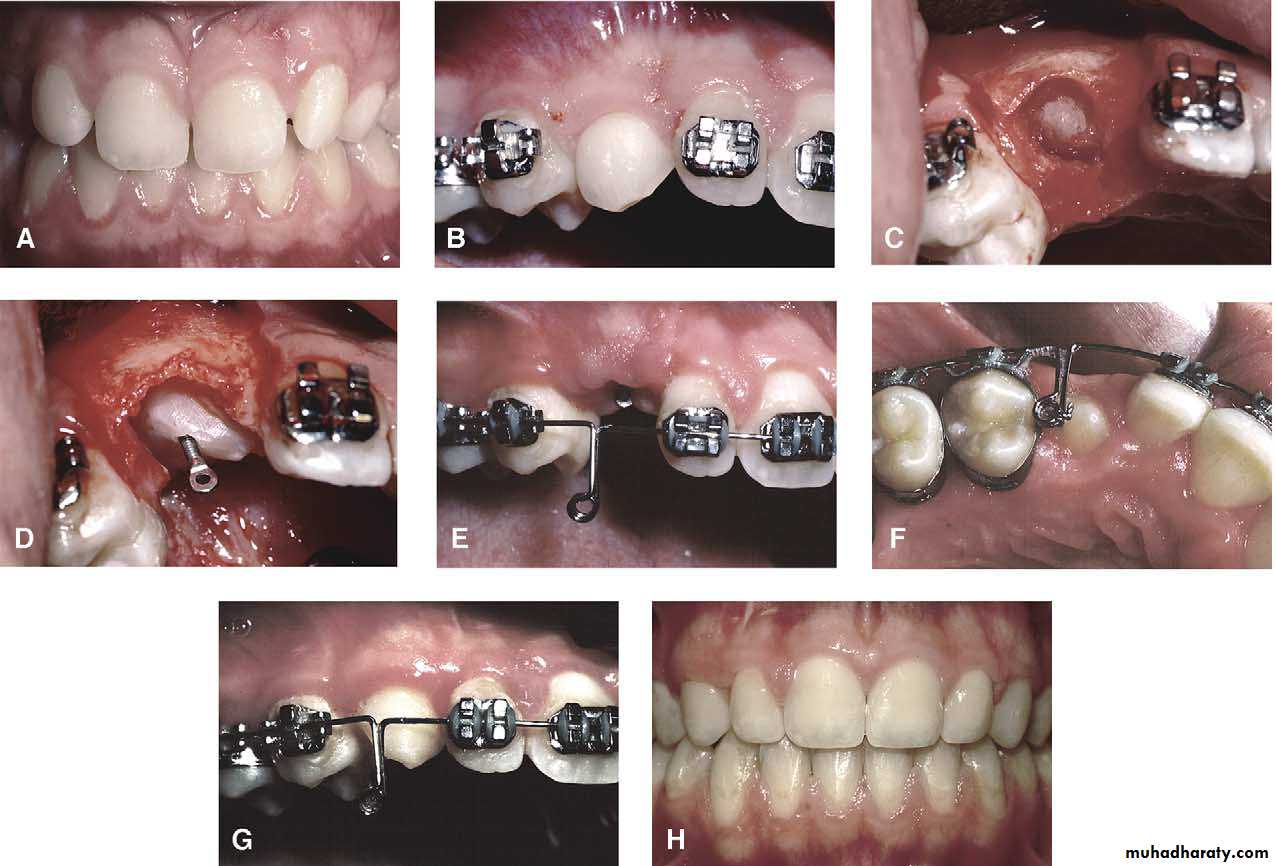

Surgical exposure :the path of eruption is not obstructed

Surgical exposure with orthodontic traction: the path of eruption is obstructed

Surgical exposure with orthodontic treatment (palatal approach )